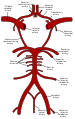

شراين متفرعة من العنق. تتفرع الشرايين السباتية الغائرة من الشرايين السباتية الأصلية - موضحة على الشكل باسم Common caroti on the figure. | |

الشريان السباتي الغائر، يقع على الجانب الداخلي من العنق على الجانب المقابل للشريان السباتي الظاهر.[1] في التشريح البشري، تتفرع الشرايين السباتية الغائرة من الشرايين السباتية الأصلية حيث تتشعب هذه الشرايين السباتية الغائرة والظاهرية عند مستوى الفقرة العنقية 3 أو 4؛ يوصل الشريان السباتي الغائر الدم للمخ بما في ذلك العينين،[2] بينما يوصل الشريان السباتي الظاهري الدم لمناطق أخرى في الرأس، مثل الوجه، فروة الرأس، الجمجمة، والسحايا.

يتم تزويد المخ بالدم عن طريق 4 شرايين هي الشريانان السباتيان الغائران والشريانان الفِقريان[3]. لا يتفرع الشريان السباتي الغائر حتى يدخل الجمجمة من خلال النفق السباتي أسفل الجمجمة. بعد دخول الجمجمة يسير الشريان السباتي على شكل حرف S إلى جانب السرج التركي (باللاتينية: Sella turcica) مروراً بالجيب الكهفي (باللاتينية: Sinus cavernosus) لينقسم إلى فروعه الرئيسية:

- الشريان العيني (باللاتينية: Arteria ophthalmica) والذي يزوِّد العين بالدم.

- الشريان المخّي الأمامي (باللاتينية: Arteria cerebri anterior) والذي يزود الجزء الأمامي للدماغ بالدم.

- الشريان الموصِّل الخلفي المُخِّي وهو جزء من الدائرة الشِّريانية الدِّماغية (باللاتينية: Cirulus arteriosus).

ثم يتغير أسم الشريان السباتي الغائر ليشكل الشِّرْيانُ المُخِّيُّ الأَوسَط، هذا الشريان الذي يعتبر امتداداً للشريان السباتي الغائر، والذي يزود الجزئين الجانبيين من الدماغ.